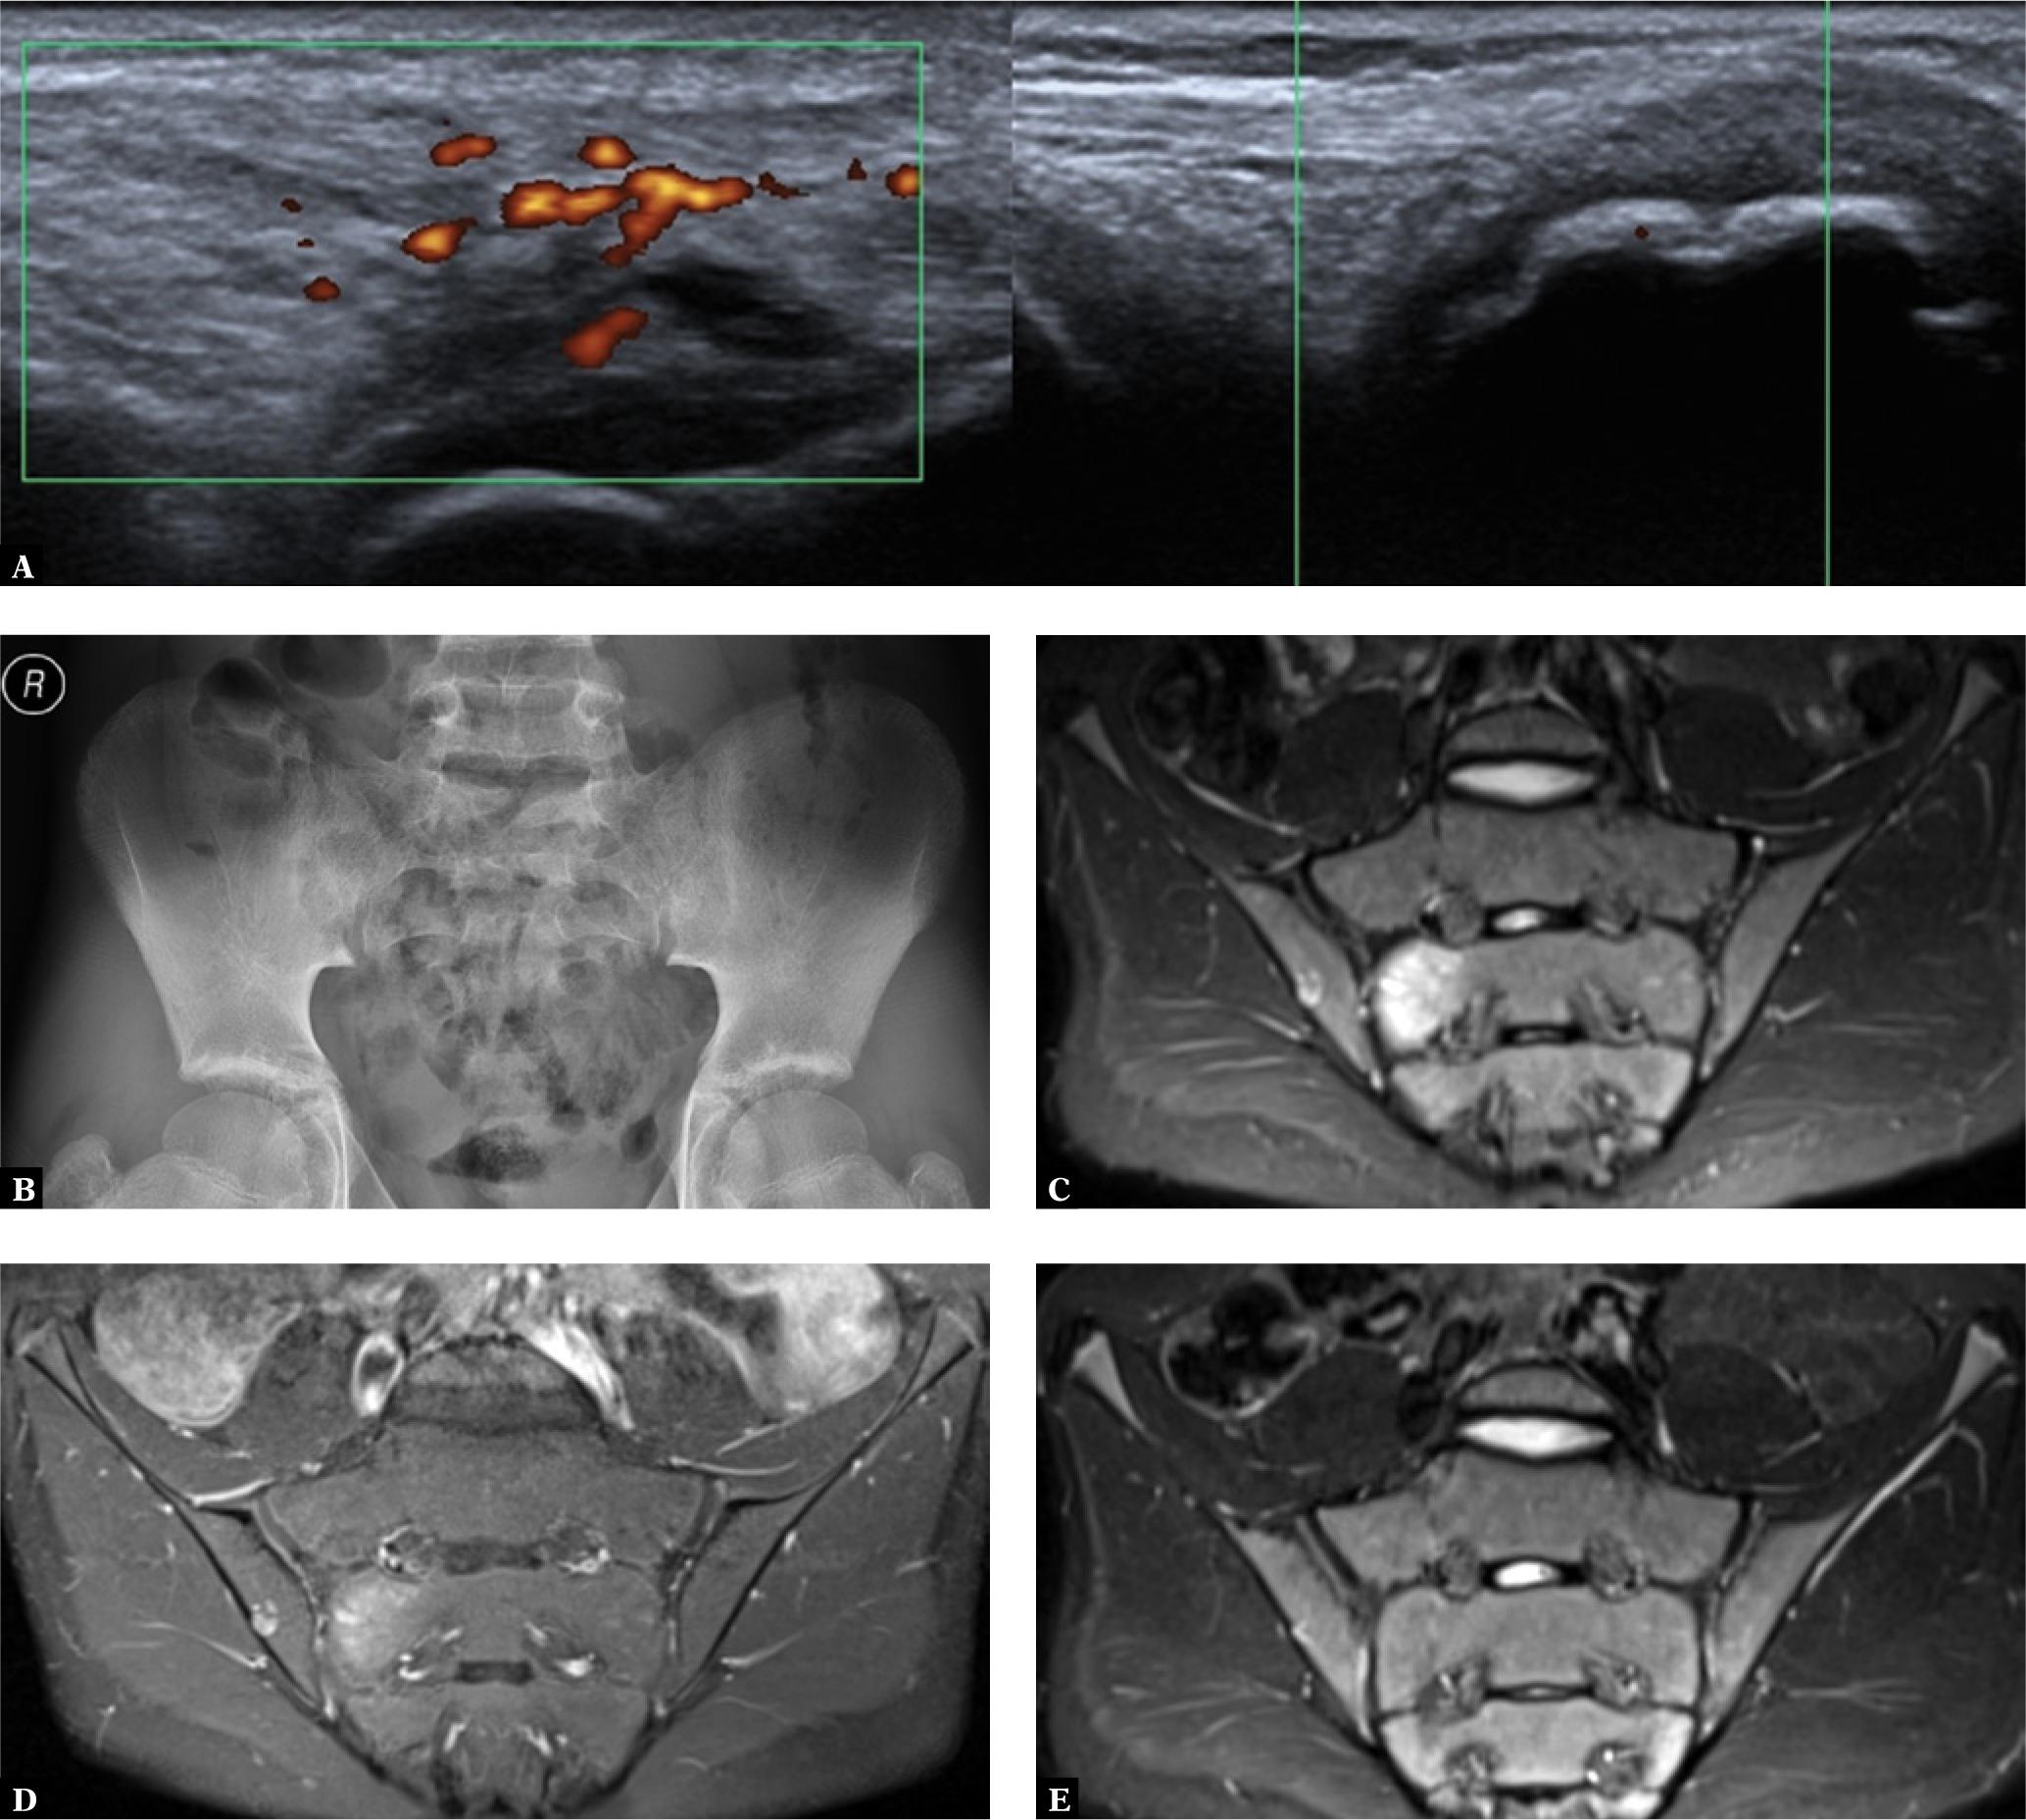

Radiographic spine and sacroiliac joint changes are typically not present in early stages(16). If sacroiliitis occurs, similar to adults with SpA, the earliest stages may only be visualized on MRI (Fig. 1). According to the ASAS (Assessment of Spondyloarthritis International Society) criteria used in adults with SpA, patients should have an MRI when a radiograph does not fulfill the modified New York criteria for AS(21). Such criteria have not been established for children and adolescents with JSpA. Furthermore, to date none of the classification criteria or imaging recommendations include MRI for diagnosing early inflammatory changes in axial SpA in children and adolescents(21–23). Bollow et al.(24) used MRI to detect active inflammatory changes in patients with normal radiographs. Tse et al.(10) and Jaremko et al.(25) showed MRI to have a higher sensitivity than radiography in diagnosing sacroiliitis. Lin et al. (13) discovered that in contrast to adults, SI joint synovitis in children could be an independent risk factor of inflammation, without accompanying bone marrow edema (BME). Herregods et al. (26) found that increased fluid signal in the joint cavity, without other imaging features of sacroiliitis (e.g. BME), was insufficient abnormality to confirm the diagnosis of JSpA in children. These are examples of some controversies in MRI of sacroiliitis in children, which suggest that there is a need for more research in this area.

A 14 year-old boy with JSpA: A. ultrasound of the right knee: the right iliotibial band enthesitis is seen, and no more pathologies; normal iliotibial band in the left knee (right site of the image); B. a pelvic AP radiograph: ambiguous bilateral sacroiliitis with suspected dilated joint width – grade 1 or 2 bilaterally; C. an oblique coronal, T2-weighted and fat-suppressed MRI image; D. a T1-weighted fat-suppressed image after contrast injection: intensive BME in the right second segment of the sacrum and a smaller one in the right iliac bone with a signal increase after contrast injection compatible with sacroiliitis; E. 2 years later; a follow-up oblique coronal T2-weighted fat-suppressed MRI image – resolution of the inflammation

In the initial phase, asymmetric unilateral changes may be seen on radiographs, but eventually the classical bilateral, symmetric joint involvement occurs, with erosions, reactive sclerosis and eventually partial ankylosis(17). In most cases, utmost grade 2 of sacroiliitis is seen. Rarely do children progress to sacroiliac fusion. Diffuse osteopenia of the pelvic bones may be seen as a late change due to immobilization(16,17). Very rarely, the spine is involved, but in such cases radiographs may show erosions and sclerosis, particularly at vertebral margins(16).